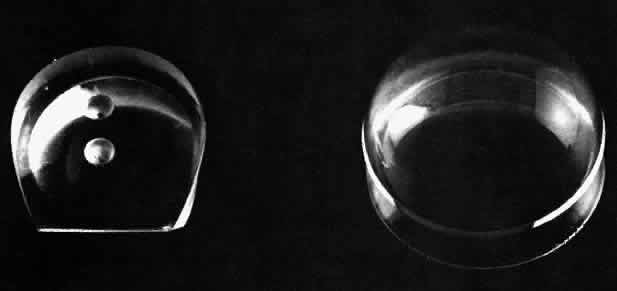

The Goldmann lenses have a radius of curvature of 7.4 mm, which is steeper than the normal cornea. The Zeiss four-mirror lens (and other similar lenses) has a somewhat flatter base with a 7.85-mm radius of curvature. Because of this the Zeiss lens is used with just the normal tear film as a liquid bridge between the lens and cornea, while the Goldmann-type lenses require the use of a more viscous bridge such as methylcellulose. The Zeiss lens has a much smaller diameter base (Fig. 8). Its internal diameter is 9 mm, or in other words less than the corneal diameter. The one- or two-mirror Goldmann lenses have a 12-mm internal diameter. The three-mirror Goldmann lenses have a diameter of 15 mm.

Fig 8. Front and back views of the Zeiss four-minor gonioscopy lens.